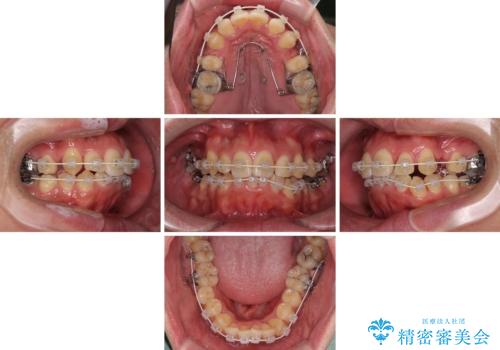

狭くて前方に飛び出した歯列 拡大装置を併用したワイヤー抜歯矯正治療

- デコボコと前歯の突出感を気にして来院された患者様です。

舌の突出癖などにより上顎前歯が前方に突出し、さらに歯列幅が狭小になっている状態でした。

また、上顎歯列全体が下顎に対して前方位に位置していました。

上顎歯列幅を側方に拡大するとともに、歯列全体を後方に移動させるためのアンカースクリューと補助装置を使用し、上顎左右第一小臼歯2本、下顎左右第二小臼歯2本、計4本を抜歯し、ワイヤー装置にて矯正治療を行うこととしました。

上下前歯の前後差が非常に大きく、3年以上の治療期間が予想されましたが、無事に3年間ちょうどで仕上げることができました。